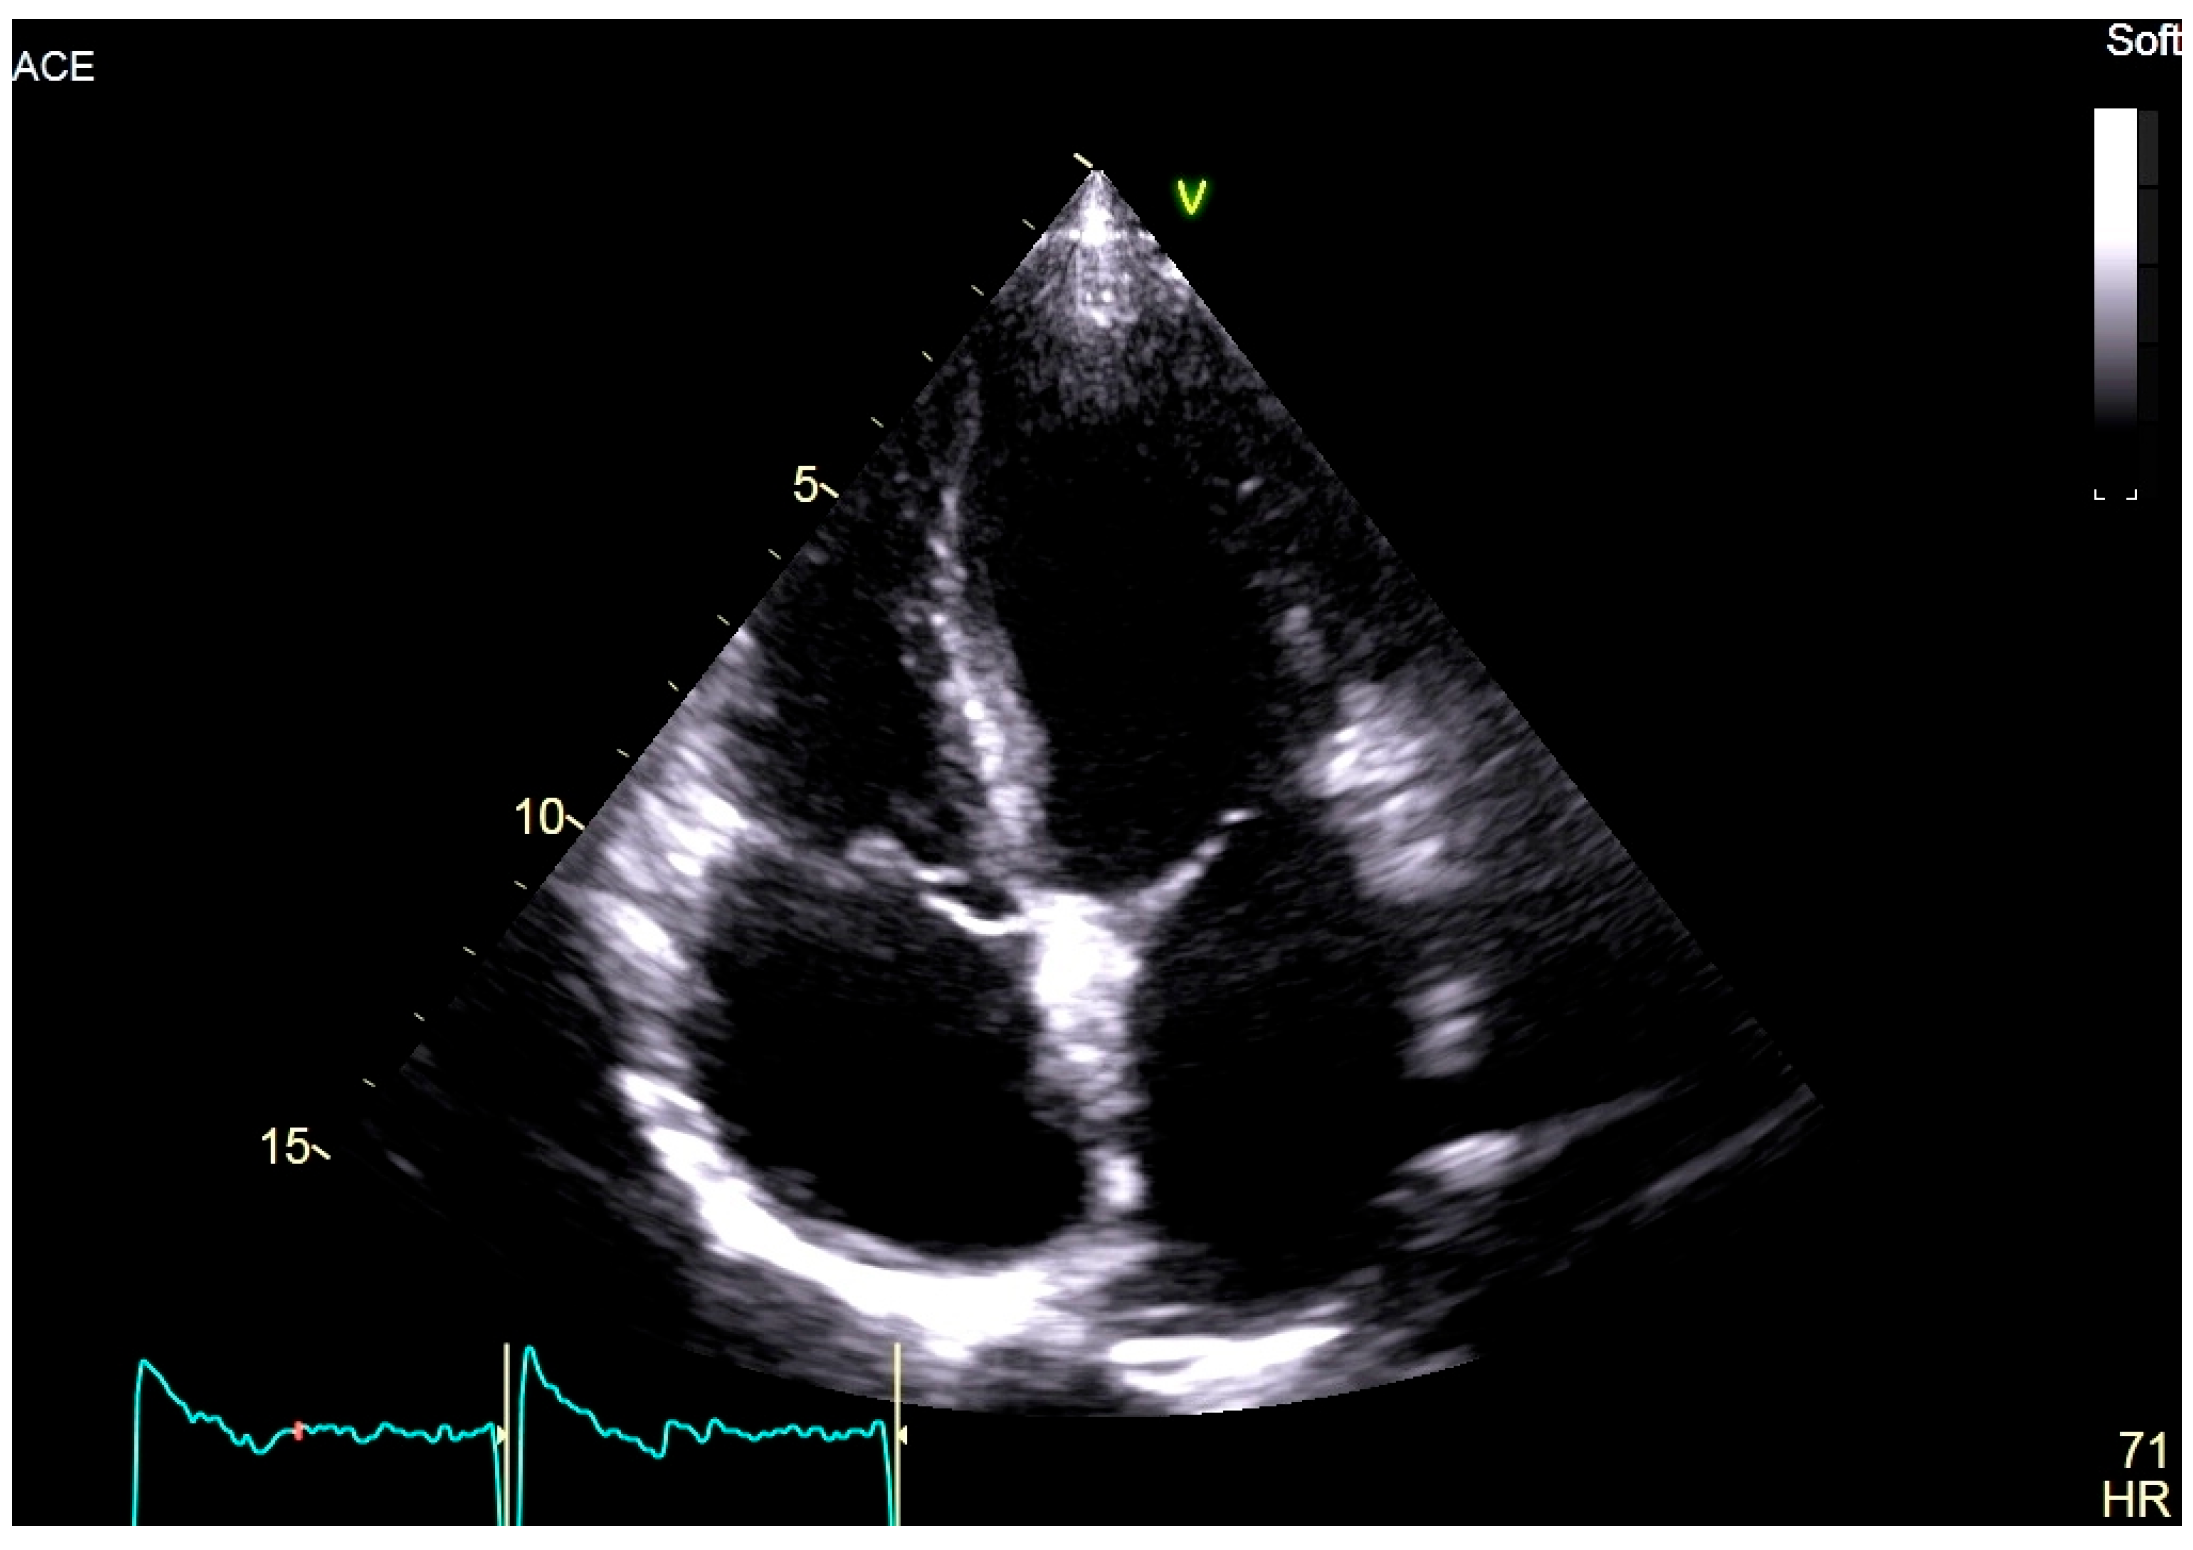

At the age of 18, the patient complained of palpitations during physical activity, and an episode of atrial flutter after a gastrointestinal infection was also documented. An implantable loop recorder was subsequently implanted for the purpose of defining the burden of AF and detecting asymptomatic episodes. More recent echocardiography revealed biatrial dilatation (left atrium diameter: 38 mm; left atrium volume index: 39 mL/m2; right atrium area: 21 cm2), mild mitral regurgitation, and preserved biventricular function (left ventricular ejection fraction: 58%) (Figure 2).

Figure 2. Two-dimensional transthoracic echocardiography, apical 4-chamber view of the proband, showing marked biatrial enlargement with preserved biventricular size and systolic function.